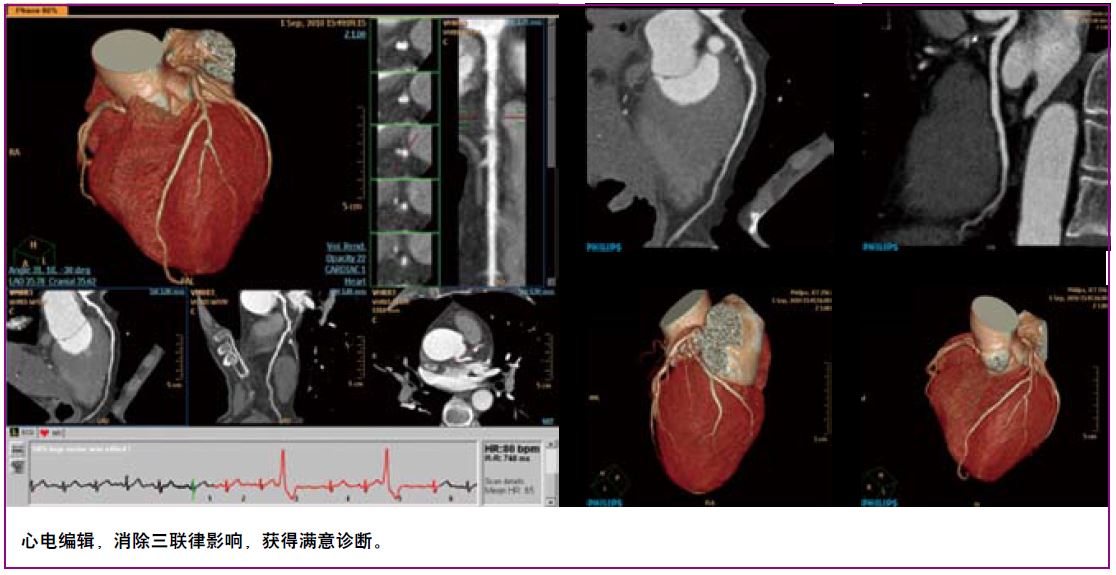

凭借0.27秒/圈极速旋转,8厘米宽体覆盖以及完善的解决方案,极速CT令心脏检查驾轻就熟。